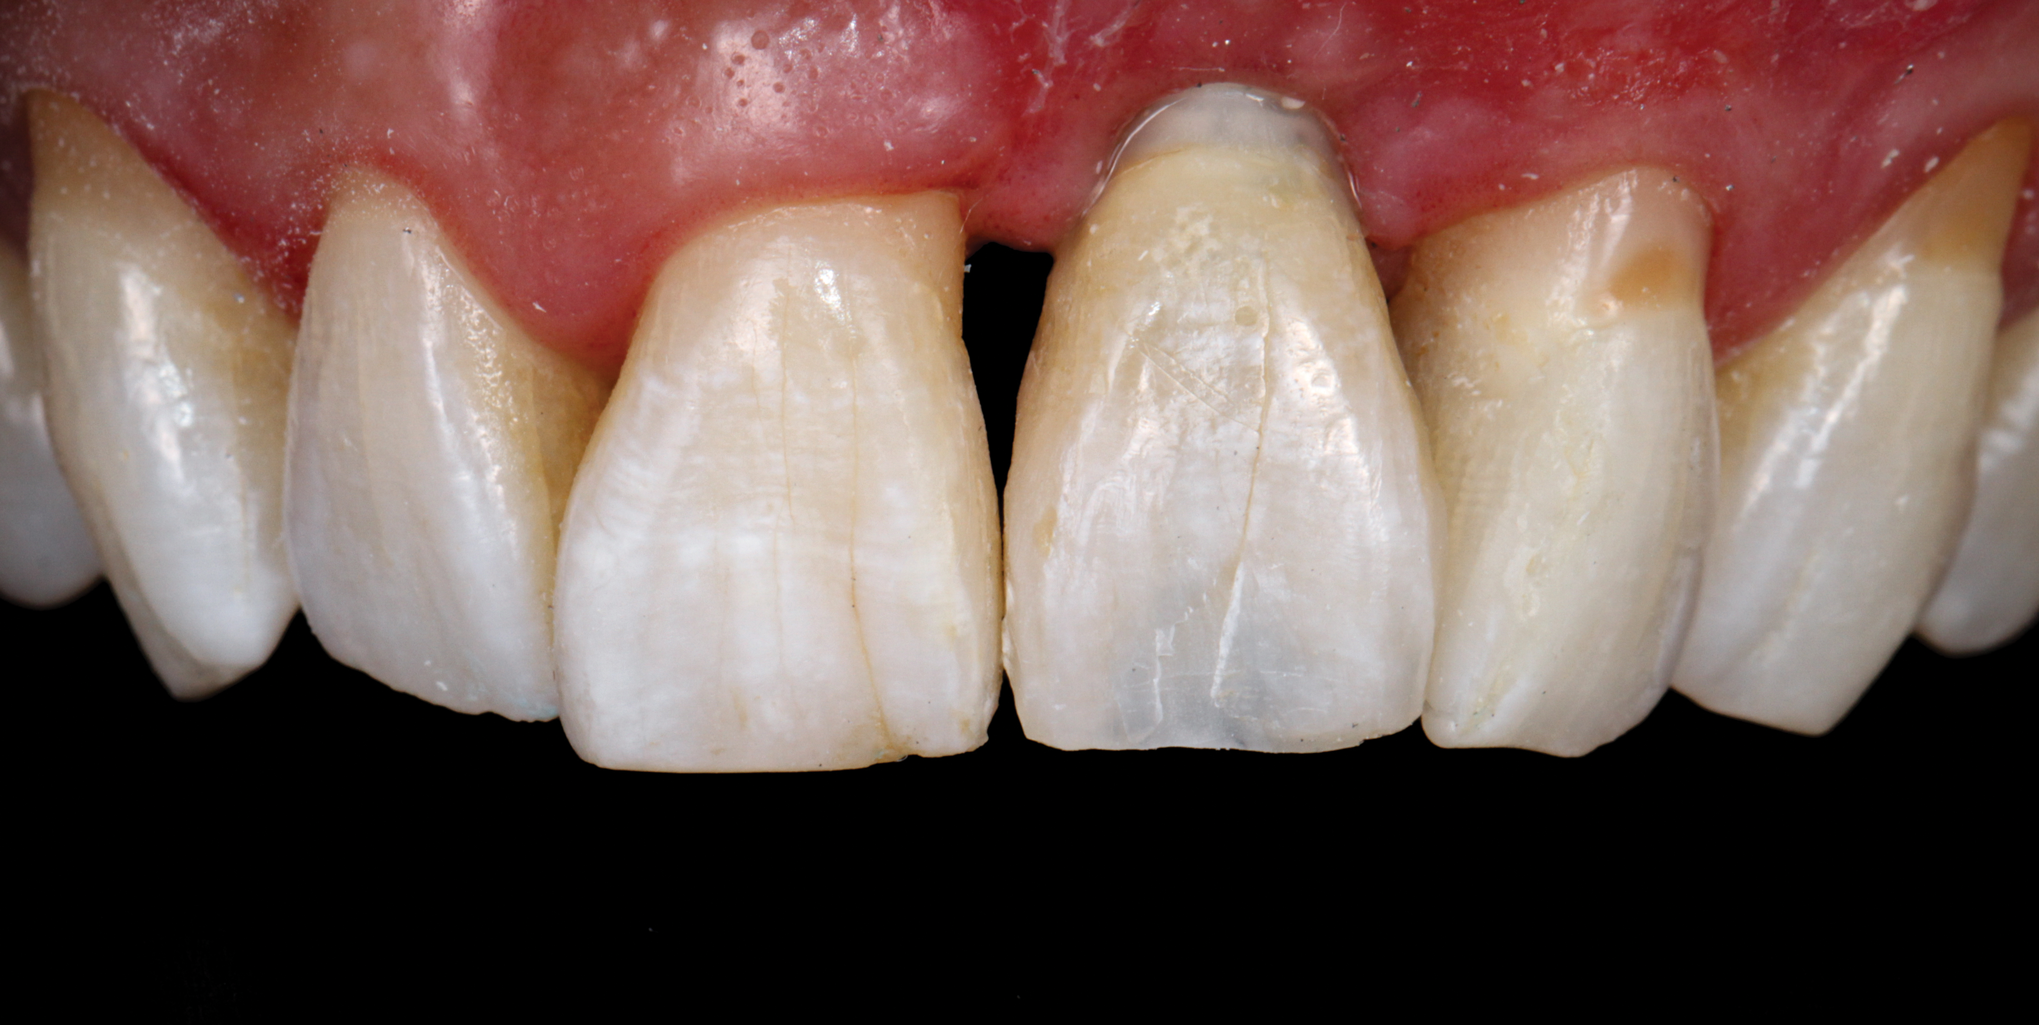

To demonstrate the principles and protocols described in this article, three case examples are included. The first case involves the treatment of a patient who sought replacement of the maxillary left canine (tooth No. 11) with an implant-supported restoration (Figure 11 through Figure 34), and in the second case, the patient presented for replacement of the maxillary left central incisor (tooth No. 9) (Figure 35 through Figure 44). In the third case, the patient also presented for replacement of the maxillary left central incisor (tooth No. 9) but had a preexisting bonded pontic made from the natural tooth. This was utilized in lieu of a composite tooth shell to fabricate the immediate provisional restoration. (Figure 45 through Figure 57).

(44.) The provisional restoration was placed back on the implant and tightened to 15 Ncm while applying counter torque. Note that the papillae are partially supported without pressure and that the gingival embrasures are slightly open to allow incisal migration of the papillae during the integration and maturation phase.

Figure 44

(56.) The provisional restoration was delivered and tightened to 15 Ncm while applying counter torque. Note that there is no pressure on the surrounding tissues and that the gingival embrasures were left open to allow for maximum incisal migration of the gingiva and papillae. The palatal and incisal surfaces were evaluated and modified to ensure that there was no contact throughout the excursive range.

Figure 56

(57.) The provisional restoration was delivered and tightened to 15 Ncm while applying counter torque. Note that there is no pressure on the surrounding tissues and that the gingival embrasures were left open to allow for maximum incisal migration of the gingiva and papillae. The palatal and incisal surfaces were evaluated and modified to ensure that there was no contact throughout the excursive range.

Figure 57